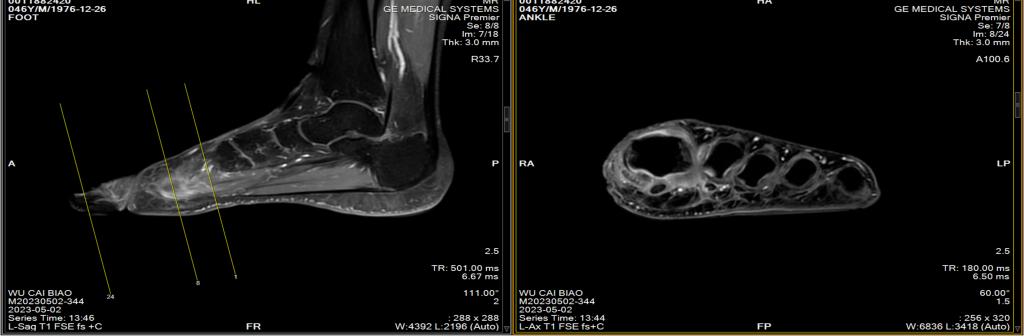

磁共振左足平扫增强

左足第一跖骨、第一足母趾近节趾骨、第一趾远节趾骨及第三趾中节趾骨多发异常信号灶,周围软组织肿胀,性质待定:炎症?请结合临床。

图B:患者趾骨水肿

图E:MRI根骨水肿

MRI(金标准):T2加权像高信号(骨髓水肿),增强后强化,可发现早期无症状病灶。